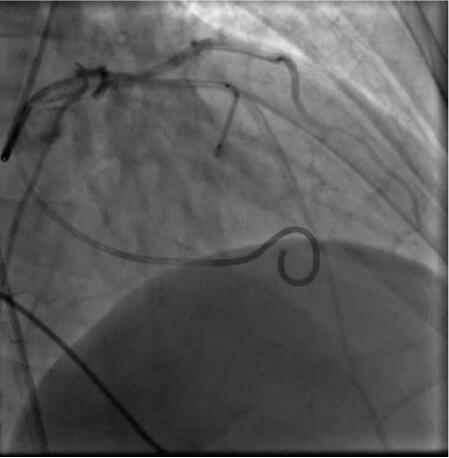

6﹒左室造影、冠脉造影、心腔测压

左主干、前降支、回旋支、右冠状动脉光滑无狭窄,左心室与主动脉压力阶差为80mmHg,应激后压差140mmHg,呈典型的主动脉瓣下狭窄曲线。左室造影可见流出道梗阻。

(四)化学消融步骤

选择暴露左前降支第一间隔支最清楚的体位(一般为右前斜位15°~45°之间),将6F的PTCA导引导管置于左冠开口处,以0.014英寸钢丝进入L AD第一间隔支(S1)。根据S1粗细,选择相应的OVER‐T HE‐WIRE球囊导管,经导引钢丝将球囊导管送入S1。以4~8at m扩张球囊20~30分钟。若患者心脏听诊杂音明显减轻或压力阶差下降,证明该靶血管为“罪犯”血管;静脉推注哌替啶或吗啡后,经过球囊中心腔缓慢注入96%~99%无水酒精1.5~4.5ml(根据血管直径大小),保持球囊加压状态5分钟~10分钟),撤出球囊导管。手术消融后应激性压差<50mmHg。

(见图31‐25)

图31‐25 室间隔化学消融

术后随访6个月,临床症状明显缓解,未再发生晕厥,坚持服药,多普勒超声示:室间隔厚度16mm,左室流出道压力阶差为6mmHg。